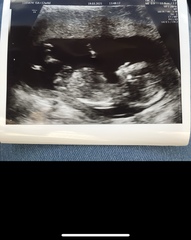

As an example these are my ultrasound direct scan pics from 12+6

Private Scan- Clinic Recommendations